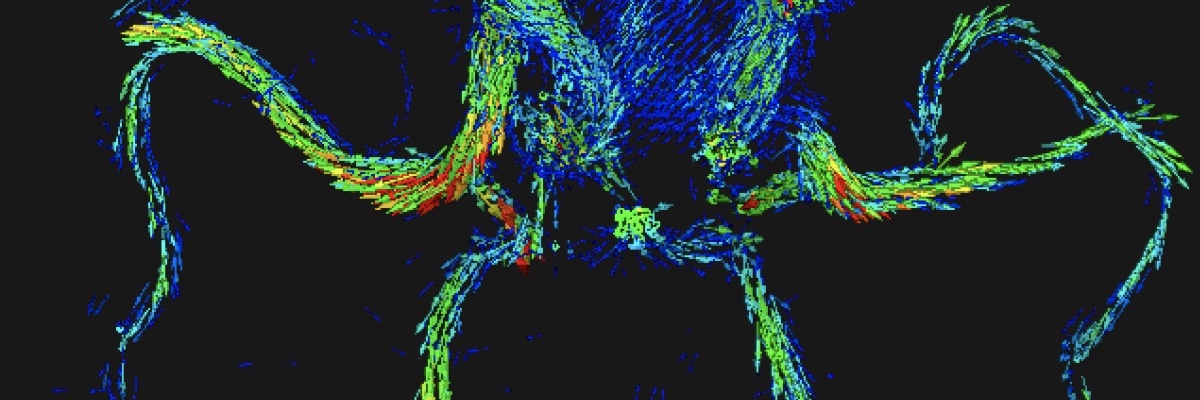

Les champs d'expertise numérique de l'équipe reposent sur les champs suivants : intelligence artificielle, image, analyse exploratoire de données, observabilité des données, analyse multiéchelle, morphologie mathématique, topologie discrète, filtrage spatio-fréquentiel, analyse dynamique, classification, décision, mesure de similarité, détection de changements, modélisation statistique.

Les champs d'expertise clinique de l'équipe reposent sur les modalités suivantes : imagerie par résonance magnétique (IRM), scanner (TDM), artériographie, imagerie nucléaire (TEP, TEMP), électroencéphalographie (EEG), échographie, imagerie préclinique (synchrotron). Les domaines cliniques privilégiés sont la néonatologie, la cancérologie, la neurologie, la radiologie, l'endocrinologie, l'urologie, l'histopathologie.